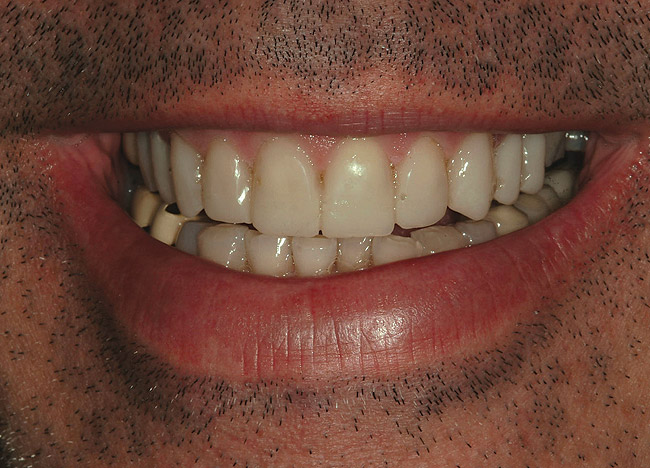

Figure 2  Preoperative view of the patient’s smile.

Figure 2